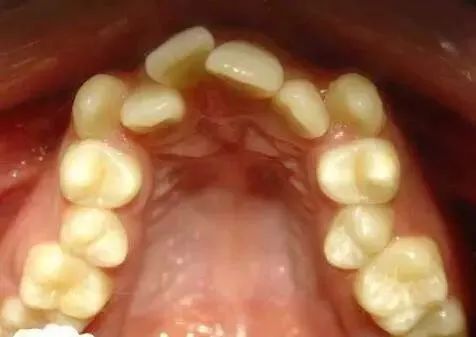

牙齿拥挤是指牙齿超出了牙床的容纳量形成牙齿过度拥挤不齐的现象。这种现象会导致牙齿排列不齐,严重影响人的正常咀嚼功能,是医学上常见的牙齿畸形状态的一种,出现牙齿拥挤应及时矫正治疗。

牙齿拥挤是牙齿错颌畸形中常见的,引起的原因很多种,如果不及时矫正处理,不仅会影响牙齿的清洁、影响上下颌牙齿之间的咬合关系,严重者会引起更多的牙齿疾病。